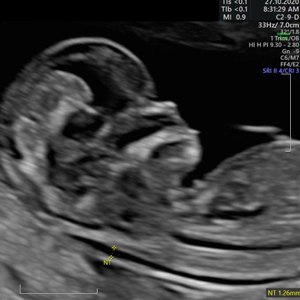

- Pionero en México en ofrecer diagnóstico por ultrasonido dentro del consultorio, así como en incorporar tecnología 3D y Doppler.